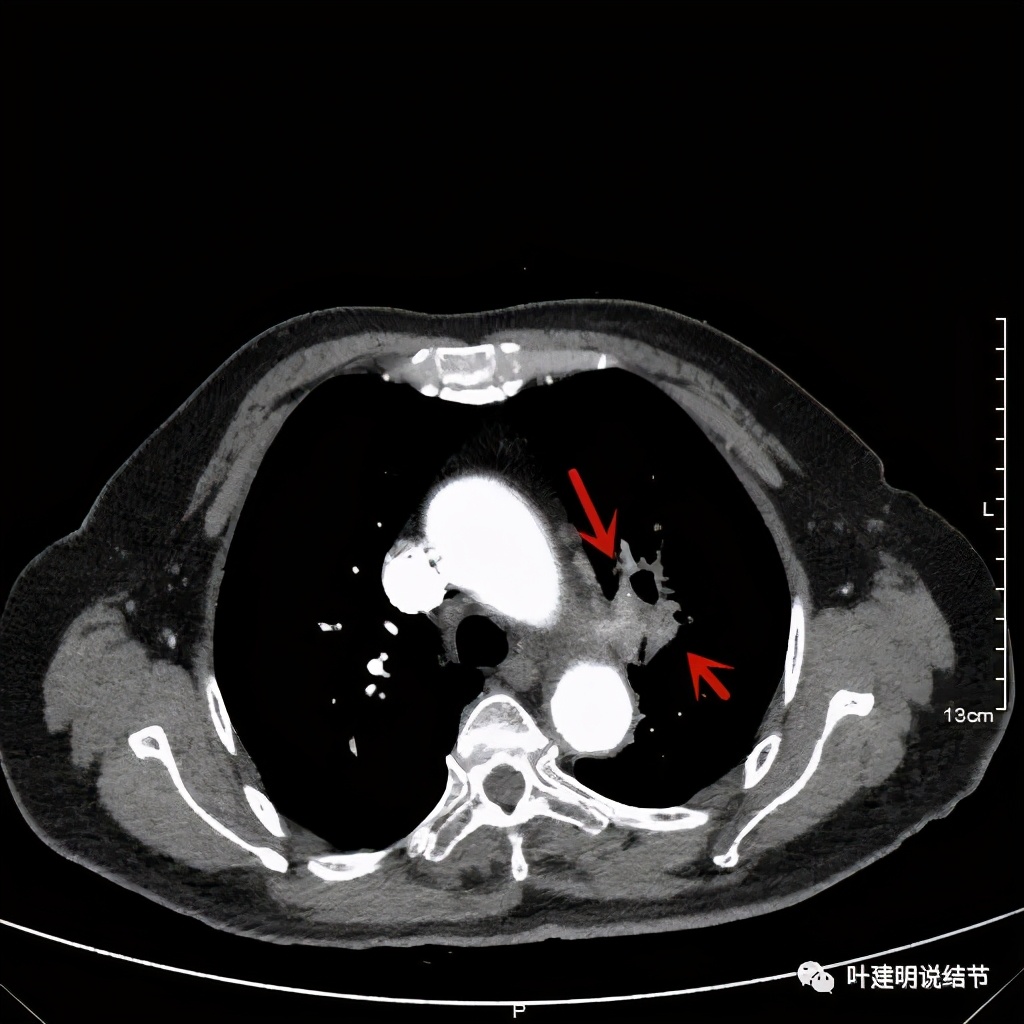

上图示主动脉弓水平仍见软组织影

上图桔色箭头示左肺动脉分支处仍被软组织(原肿瘤所在)包绕,粉色箭头示肺动脉仍与肿瘤处关系密切